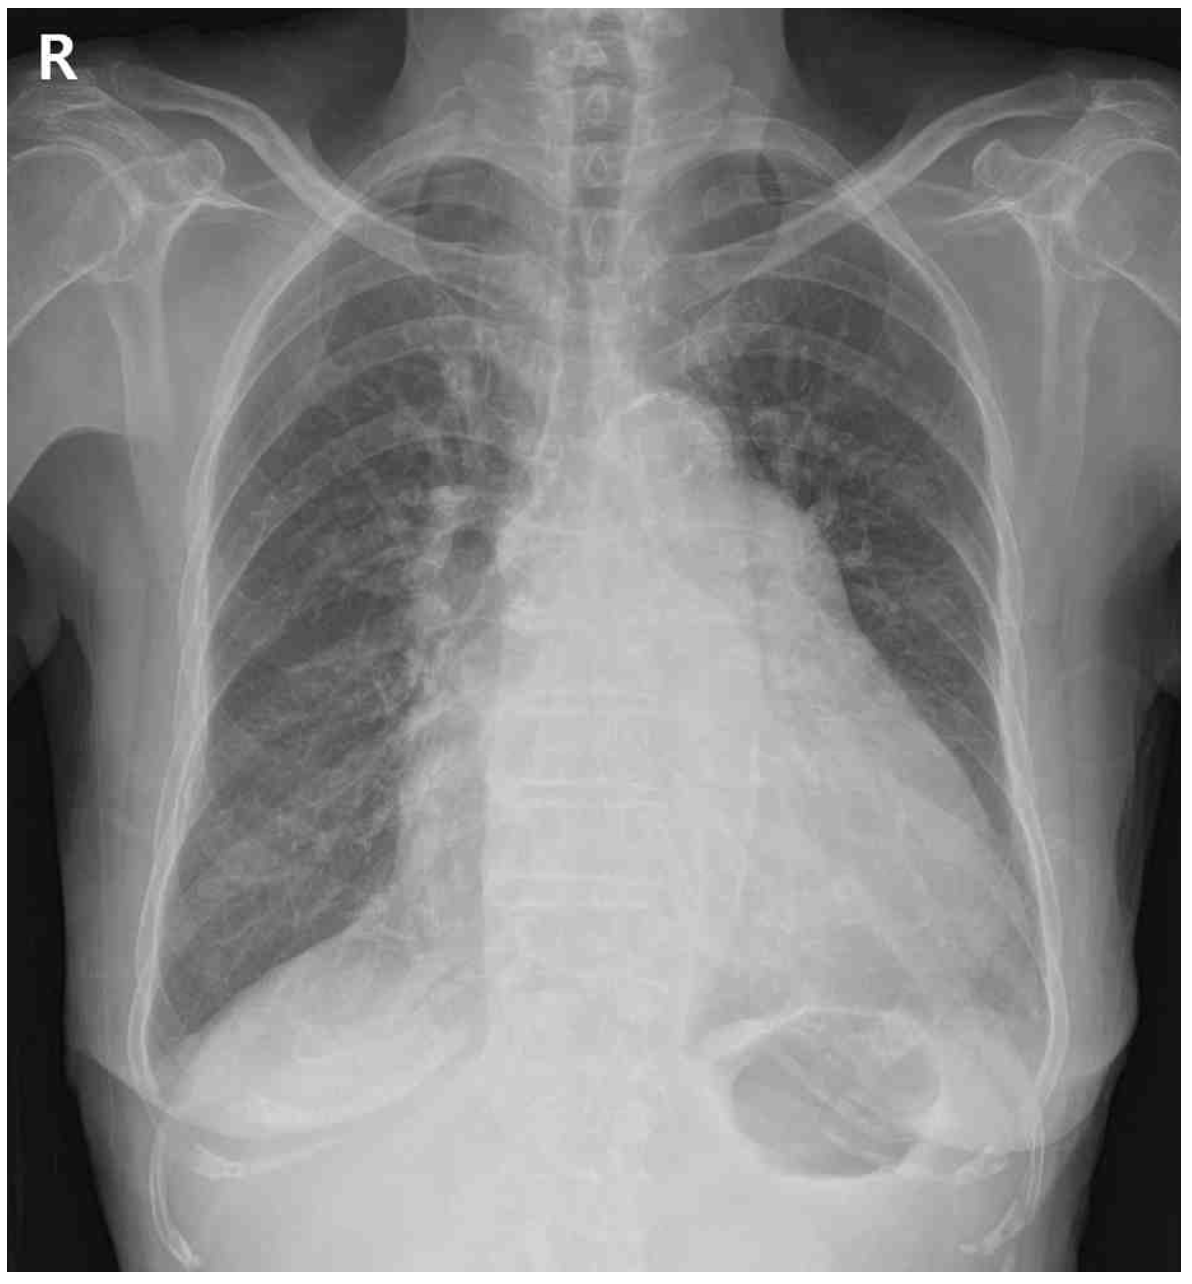

72세 여자가 6개월 전부터 숨이 차서 병원에 왔다. 호흡곤란이 1개월 전부터 점차 심해진다고 한다. 혈압 112/52 mmHg, 맥박 82회/분, 호흡 20회/분, 체온 36.1℃이다. 심음은 불규칙하지만 잡음은 없고 양쪽 등아랫부분에서 거품소리가 들린다. 가슴 X선사진과 심전도이다. 검사 결과는 다음과 같다. 진단은?

CXR: Cardiomegaly, pulmonary edema

LVEF가 50%이상이지만 혈액검사 상 BNP 상승, 좌심방 용적지수의 증가를 통해 심장의 diastolic dysfunction이 있음을 파악할 수 있고 호흡곤란과 함께 cardiomegaly, pulmonary edema, 양측 폐하부 수포음이 확인되므로 좌심실박출률보존심부전으로 진단한다.

• CXR에서 cardiomegaly, pulmonary edema가 확인되며 양측 폐하부 수포음이 들리므로 호흡곤란의 원인이 심장성 원인임을 파악할 수 있다.

• 심초음파 검사 상 diastolic dysfunction과 함께 호흡곤란, 체액저류(pulmonary edema)가 확인되므로 HF로 확진 가능하며 LVEF가 57%로 50% 이상이므로 HFpEF로 확진한다.